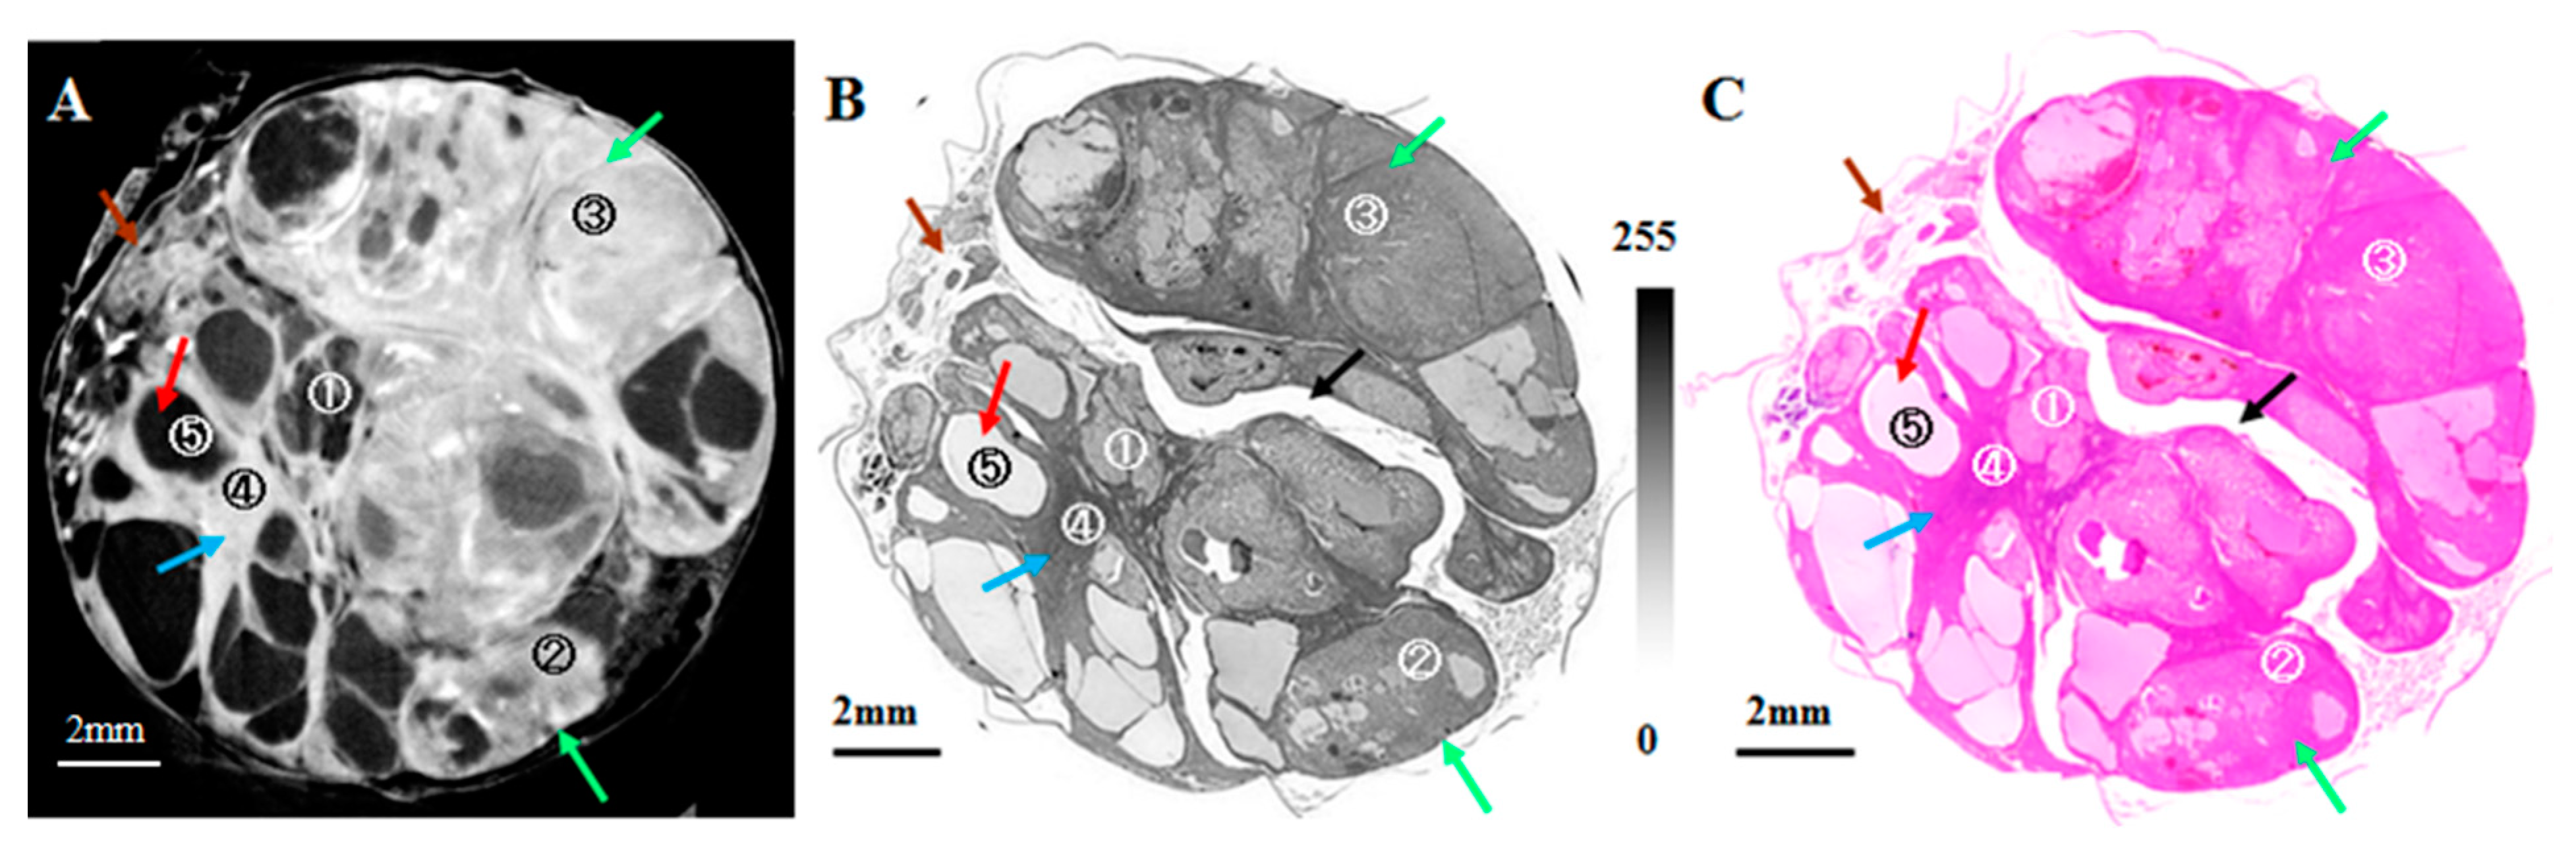

- Thet Thet, L.; Yoneyama, A.; Imai, M.; Maruyama, H.; Hyodo, K.; Takeda, T. Testicular seminoma in the aged rat visualized by phase-contrast X-ray computed tomography. Acta Radiol. Open 2018, 7, 205846011880665. [Google Scholar] [CrossRef]

- Lwin, T.T.; Yoneyama, A.; Maruyama, H.; Takeda, T. Visualization Ability of Phase-Contrast Synchrotron-Based X-ray Imaging Using an X-ray Interferometer in Soft Tissue Tumors. Technol. Cancer Res. Treat. 2021, 20, 15330338211010121. [Google Scholar] [CrossRef]